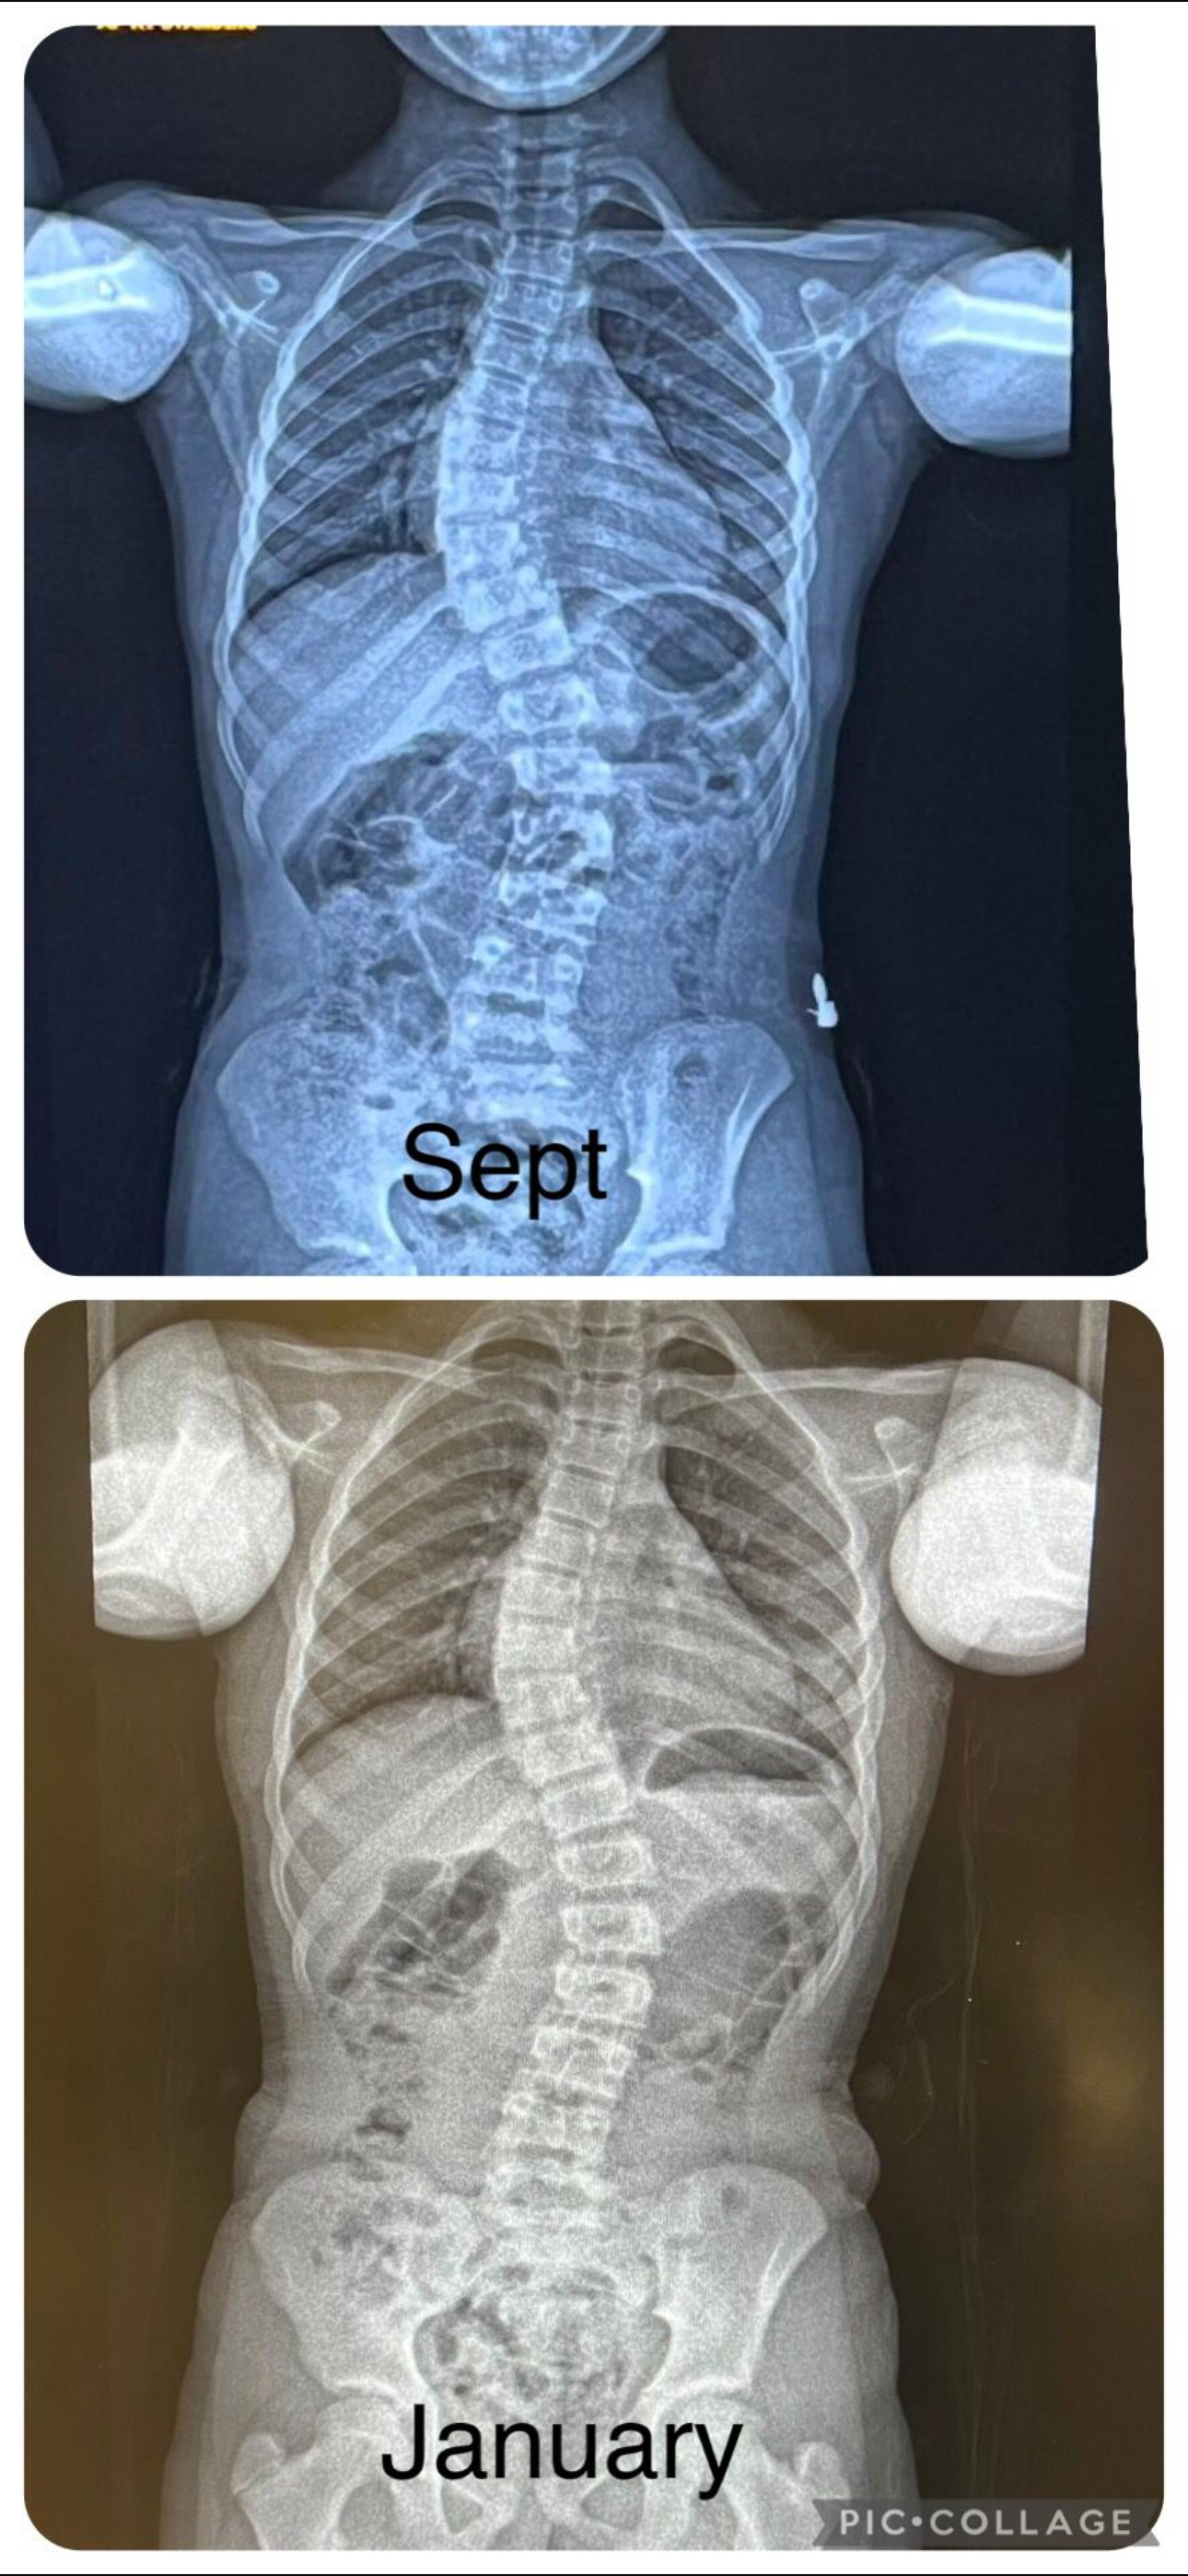

Niamh was diagnosed with scoliosis, and we began a journey none of us were prepared for. Today, we’re looking back with immense gratitude—and looking ahead with renewed hope.

In just 12 months, the change in her posture and spinal alignment has been remarkable. Her confidence has grown. Her spirit has stayed unshaken. And most importantly—she’s been able to keep dancing.